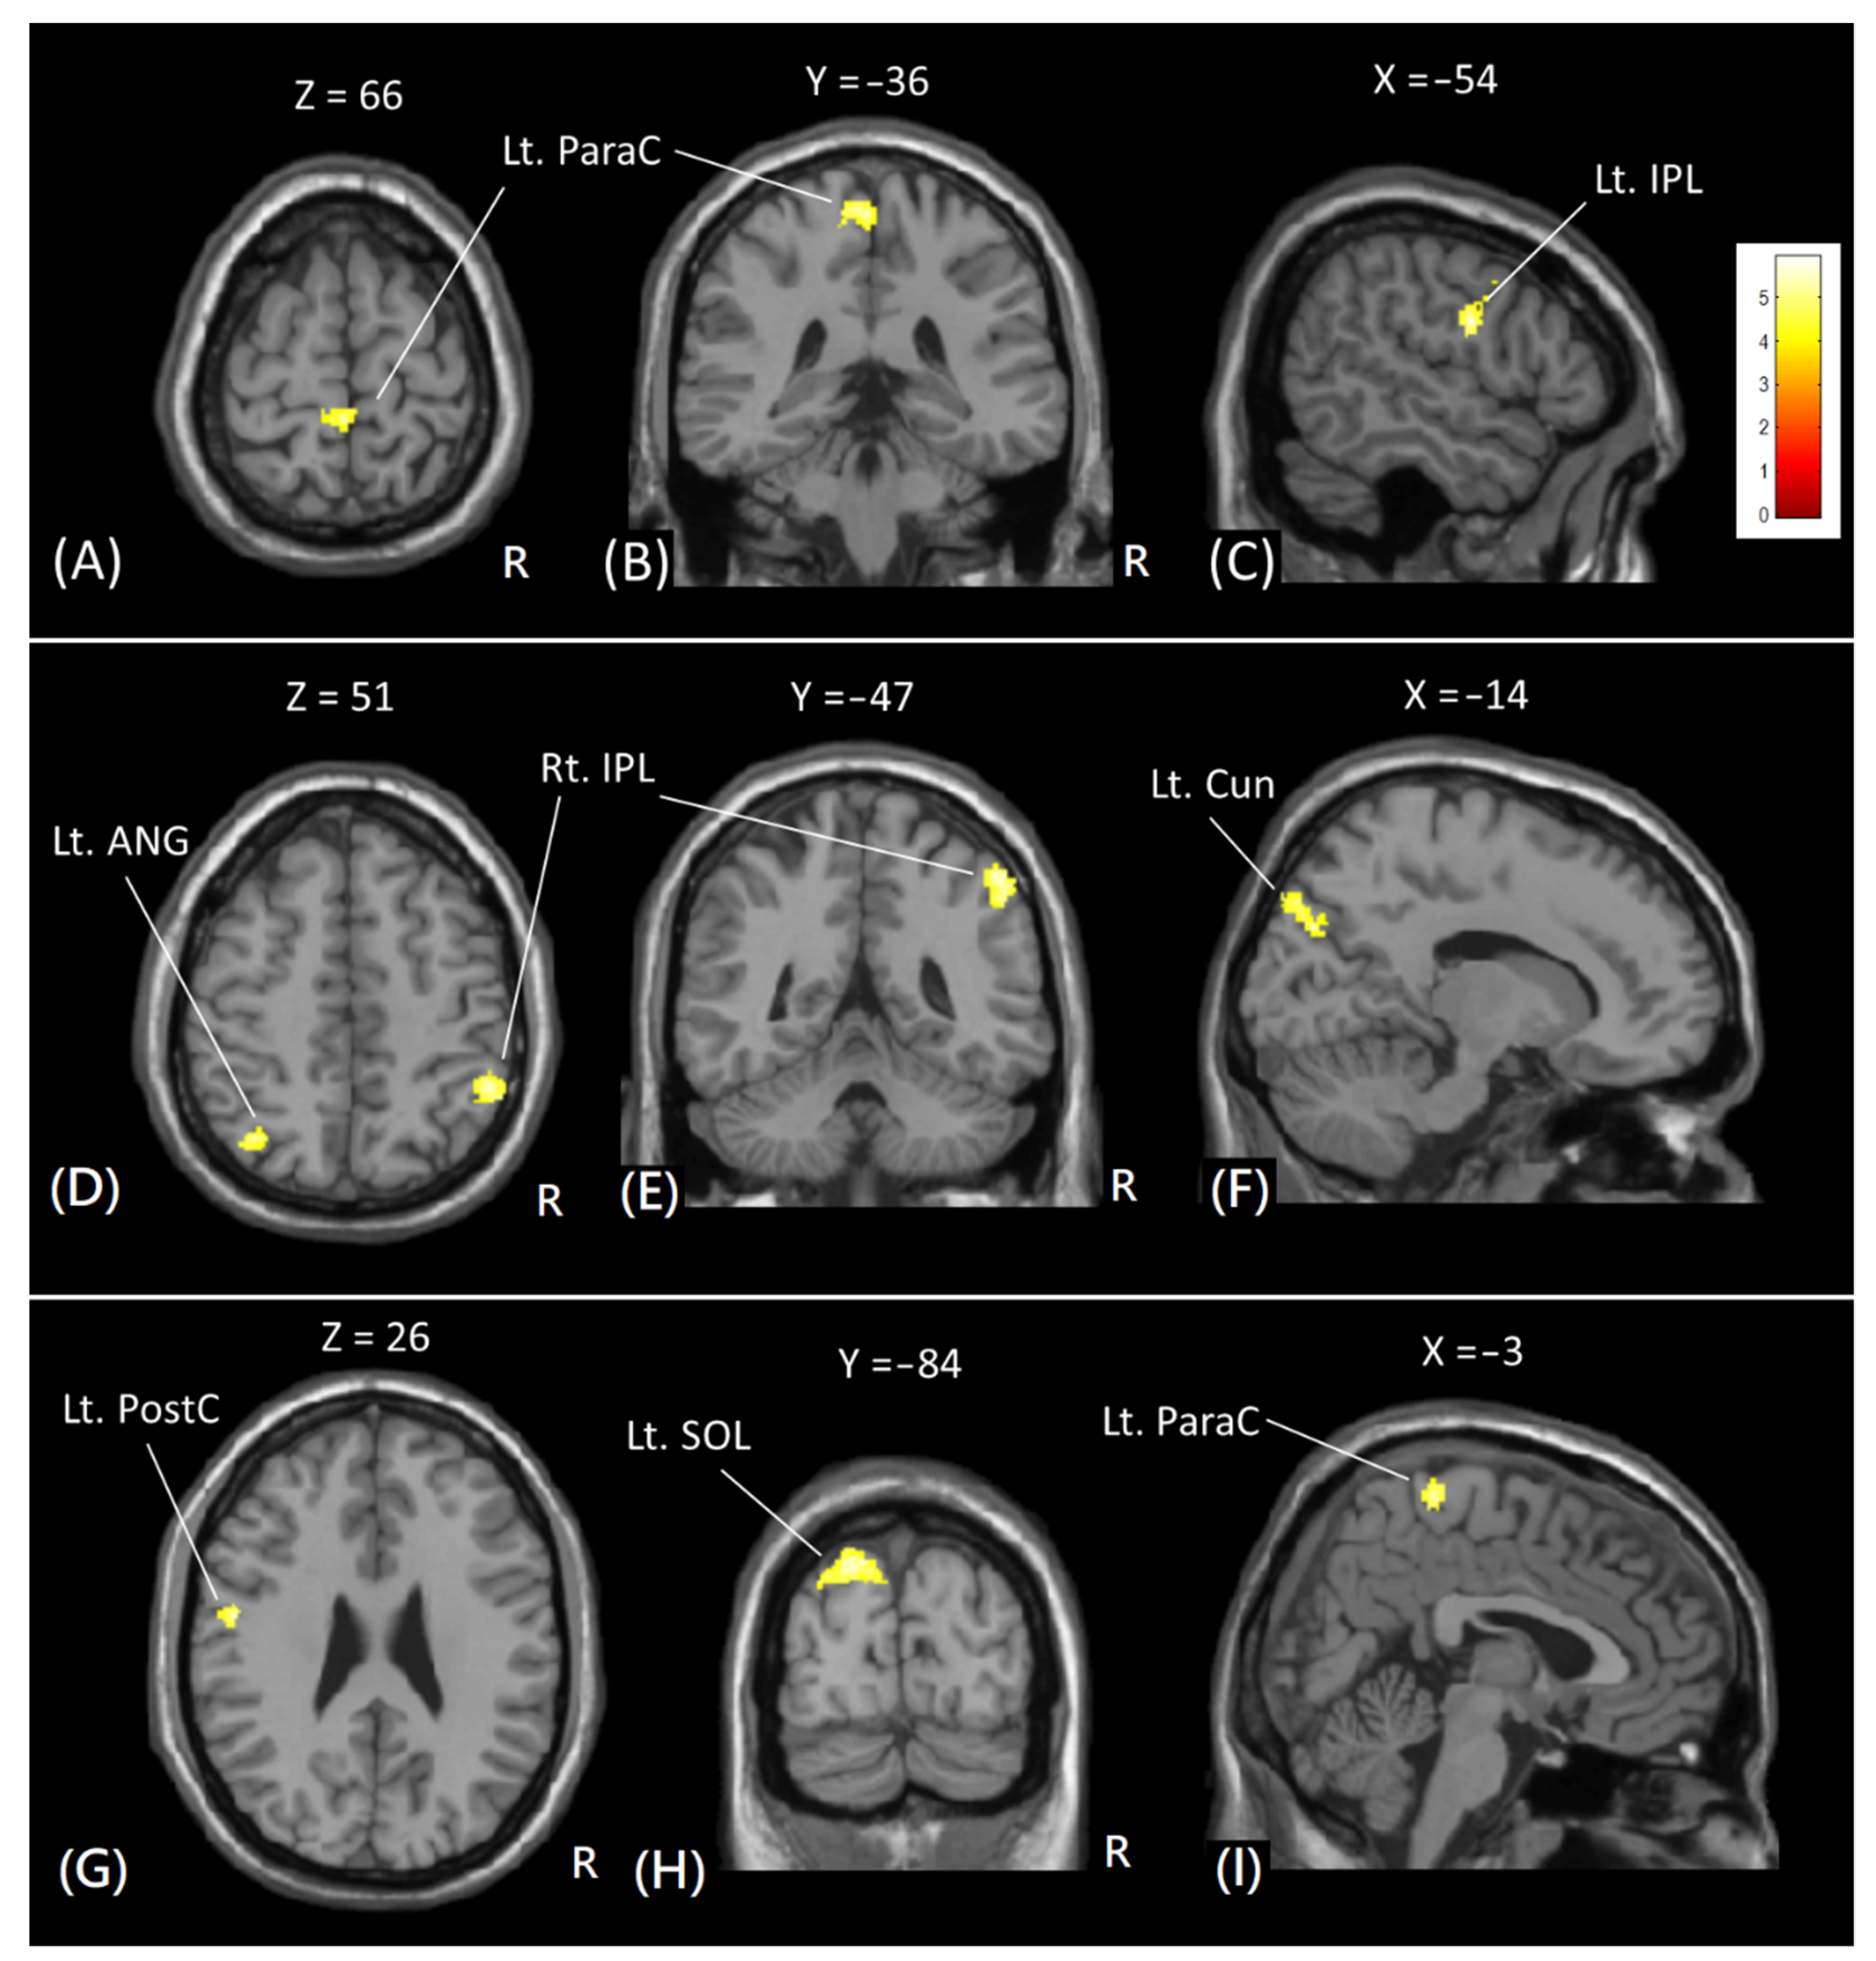

In VBM analysis, significant increases in GM volume were found in the right inferior parietal lobule, left superior occipital lobule, left cuneus, left middle occipital gyrus, left postcentral gyrus, left angular gyrus, and left paracentral lobule after 8 weeks of diabolic training, as shown in Figure 4. However, no significant decrease in GM volume was noted. Table 1 lists the Brodmann area (BA) and Montreal Neurological Institute (MNI) coordinate of significant clusters with increased GM volume with cluster-level FWE-corrected p < 0.05.

Figure 4. The voxel-based comparison of the GM volume in subjects before and after diabolo training. Red-yellow colors indicate increased GM volumes after training. Images are shown in axial (A,D,G), coronal (B,E,H), and sagittal (C,F,I) views. The color bar in the upper right corner indicates the T-value. Lt = left; Rt = right; ParaC = paracentral gyrus; PostC = postcentral gyrus; IPL = inferior parietal lobule; ANG = angular gyrus; Cun = Cuneus; SOL = superior occipital lobule.